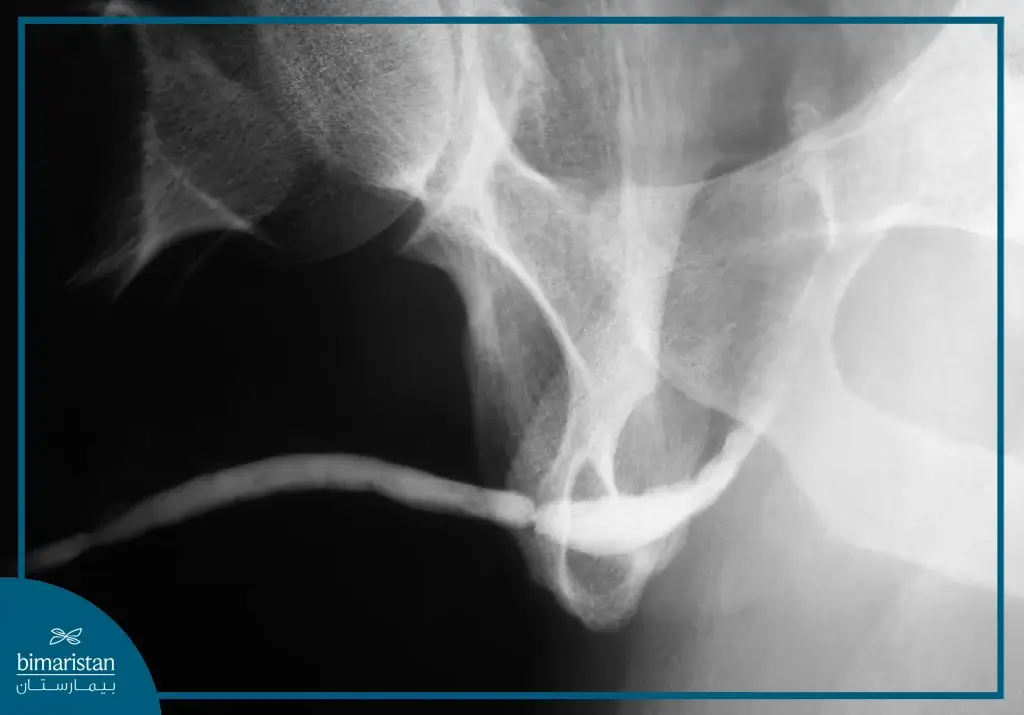

التصوير الشعاعي

يُستخدم التصوير الراجع للإحليل (RUG) كوسيلة أساسية لتحديد موقع وامتداد التضيق بدقة، وعند الحاجة قد يُجرى أيضاً تصوير المثانة أثناء التبول (VCUG) لتقييم التضيقات في الإحليل الخلفي كما في حالات ما بعد إصابات الحوض.

- تقييم ما قبل الجراحة: يتم تحديد موقع وطول التضيق باستخدام التصوير الراجع للإحليل (RUG) وتنظير المثانة لتحديد خطة الجراحة المناسبة.